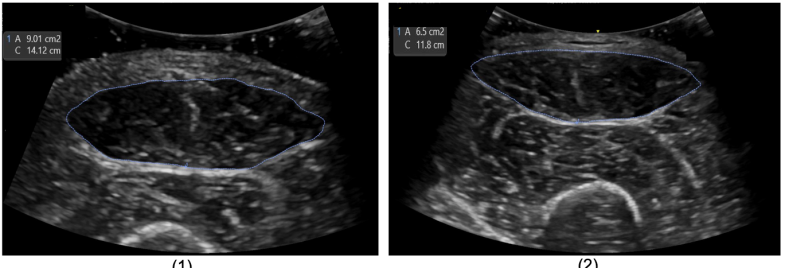

Refer to caption

Figure 1: Example of the cross-section of the rectus femoris (RF) on one ICU patient showing muscle mass reduction from admission (9cm2, left) to discharge (6cm2, right).